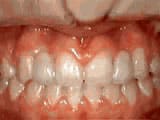

Deep overbite: lower front teeth bite into palate

Before

AfterThis adult patient, age 25, required braces and jaw surgery to correct his severe overbite. Treatment lasted two years. His problem could have been corrected without surgery if he had been treated before he was a teenager.